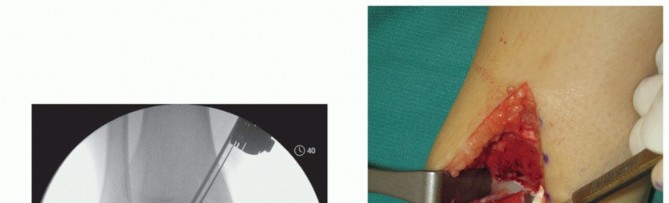

- TECH FIG 1 • (continued) G. Fluoroscopic image showing near-complete bone cut. H. Release of posterior tibial tendon sheath from distal medial malleolus to allow mobilization.

- TECH FIG 2 • A,B. Identifying the extent of the talar shoulder lesion. (continued)

There may be some irregularity to the osteotomy at the posterior margin; this is typical as the osteotomy is mobilized. It may be advantageous, as it allows for an interference fit during reduction of the osteotomy and perhaps greater stability.

Reflect the medial malleolus.

The posterior tibial tendon sheath must be released to the distal aspect of the posterior medial malleolus to allow the malleolus to reflect adequately and to gain optimal exposure of the medial talar dome (TECH FIG 1H). Protect the deltoid ligament fibers. - Preparing the Recipient Site

Define the extent of the OLT (TECH FIG 2A,B).

- TECH FIG 2 • (continued) C-E. Excision of the talar shoulder lesion using the microsagittal and oscillating saws. F. Talar shoulder lesion removed.

Excise the diseased portion of the talus (TECH FIG 2C-F).

Reciprocating and microsagittal saw (use cool saline to limit risk of heat necrosis) May need a small curette and rasp as well

Define the dimensions of the recipient site. Use a caliper and a ruler and double-check the measurements. - Harvesting Graft from Donor Talus